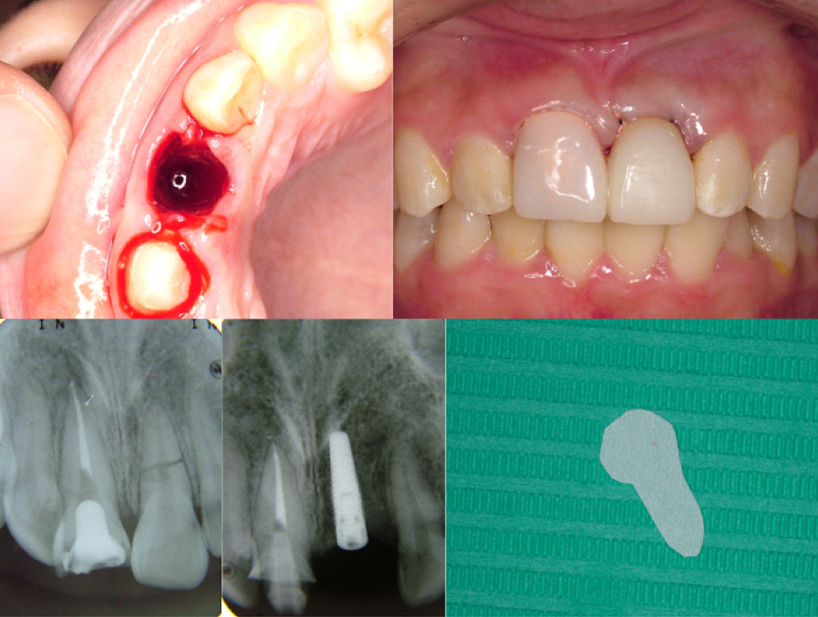

治療前治療後

| 治療内容 | インプラント奥歯1本 |

|---|---|

| 患者様の年齢 | 48歳 |

| 患者様の性別 | 男性 |

| 治療期間 | 5ヶ月 |

| 治療回数 | 25回程度 |

| 治療費用 | 50万円 |

| 治療で得られるメリット |

|

| 治療する際に起こる リスク・副作用 |